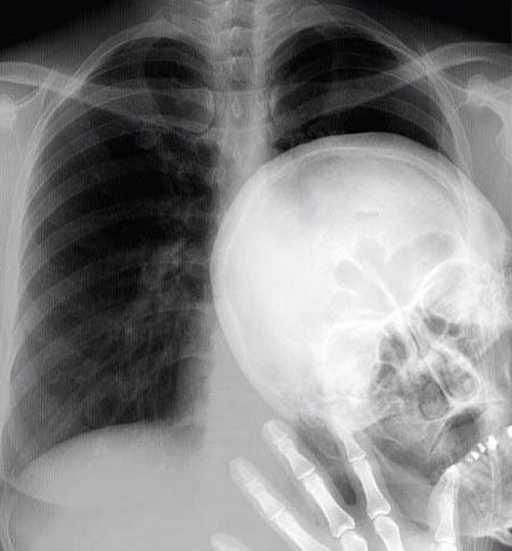

16. 这是世界上第一张X光片,由威廉·伦琴于1895年12月22日拍摄的。

一些奇怪的X光照片,看完整个人都不好了……-16.jpg